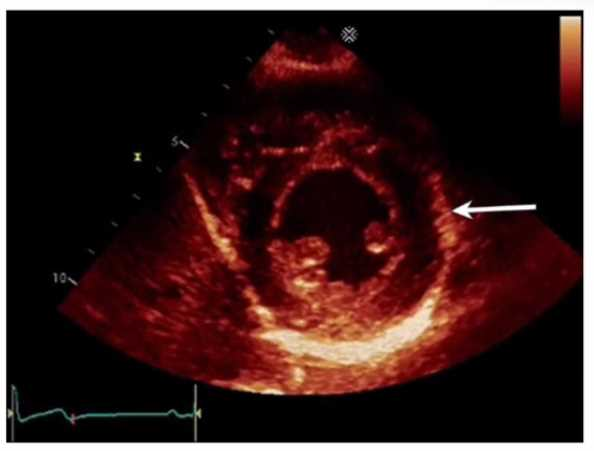

Which left ventricular regional wall segment is indicated by the arrow on this image?

1. Anterior

2. Anterolateral

3. Inferior

4. Inferolateral

Answer(s): C

The echocardiographic image shows a short-axis view of the left ventricle at the mid-papillary muscle level with segmental strain values. The arrow points to the wall segment located inferiorly (towards the bottom of the image in standard orientation), which corresponds to the inferior wall of the left ventricle.

According to the standardized 17-segment model endorsed by the American Society of

Echocardiography (ASE), the inferior wall is situated posteriorly and inferiorly in the short-axis view. The other options represent adjacent walls: anterior is opposite the inferior wall, anterolateral and inferolateral correspond to lateral wall segments.